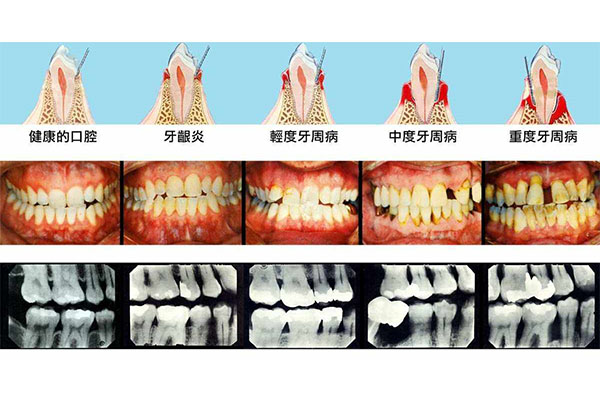

牙周病是中老年人牙齿疼痛的主要原因之一。牙周病通常由牙菌斑和牙石积累引起,导致牙龈出血、肿胀甚至牙齿松动。如果你的牙齿疼痛伴随着牙龈出血或口臭,很可能就是牙周病在作怪。中老年口腔采用先进的牙周治疗技术,能够有效清除牙菌斑和牙石,缓解牙龈炎症,帮助你恢复牙齿健康。